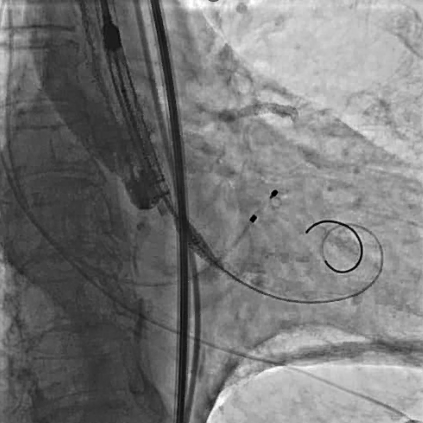

使用直头超滑导丝跨瓣后交换加硬导丝,行球囊扩张主动脉瓣,球囊扩张时行升主动脉造影,评估冠脉风险。

瓣膜定位及释放:将VenusA-Pro 23mm型号瓣膜系统送至主动脉瓣口处,以定位模式行造影,定位满意后释放瓣膜至工作位后,行定位造影,观察瓣膜位置及冠脉血流情况。瓣膜位置满意后完全释放瓣膜。